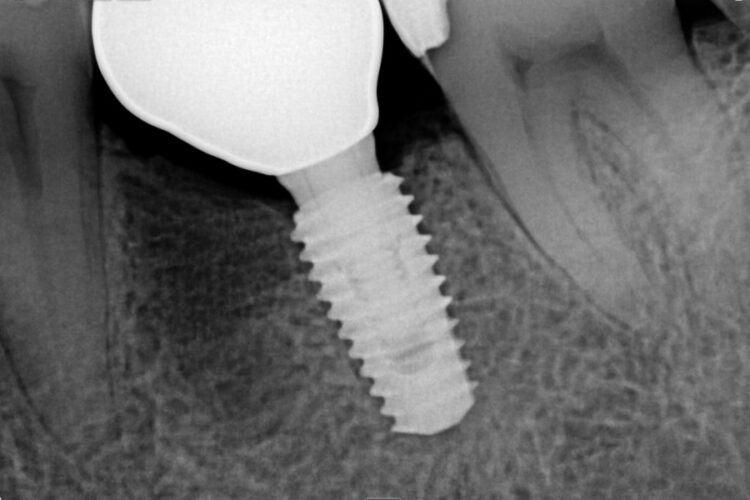

Клинический кейс имплантации

Все этапы: от компьютерной томограммы до установки коронки на имплант.

Установленный имплант: 4.5 мм на 11.5 мм

Коронка на имплант: дисиликат лития, винтовая фиксация, изготовлена в клинике за 3 часа.

Абатмент: индивидуальный титановый.

Длительность имплантации: 1.5 часа.

Промежуток от импланта до коронки: 3 месяца.

Заключение: проведена установка импланта с одновременной пластикой десны и формированием межзубных сосочков. В имплант установлен формирователь десны. Рана ушита. Швы необходимо снять через 10-14 дней. Даны рекомендации в послеоперационный период.

Установка коронки на имплант запланирована через 3 месяца.